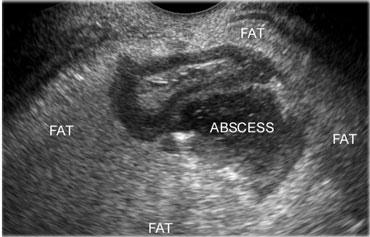

Nếu bên cạnh ruột thừa viêm phát hiện một ổ dịch, đây là dấu hiệu gợi ý áp xe ruột thừa.

Ổ dịch thường chứa khí và được bao quanh bởi mô tăng âm, không thể đè xẹp đại diện cho mạc nối và mạc treo, cũng như các quai ruột lân cận bị dày thứ phát, đang cố gắng bịt kín áp xe khỏi khoang phúc mạc.

Nếu phát hiện áp xe ruột thừa và không có viêm phúc mạc rõ ràng, dẫn lưu qua da là phương pháp điều trị được lựa chọn.

Ở những bệnh nhân ổn định không sốt và chỉ đau nhẹ, thậm chí có thể khôn ngoan khi chờ đợi áp xe tự dẫn lưu vào quai ruột lân cận.

Bên trái là hình ảnh ổ áp xe chứa sỏi phân.

Lưu ý ruột thừa viêm (mũi tên) nằm cạnh ổ áp xe.